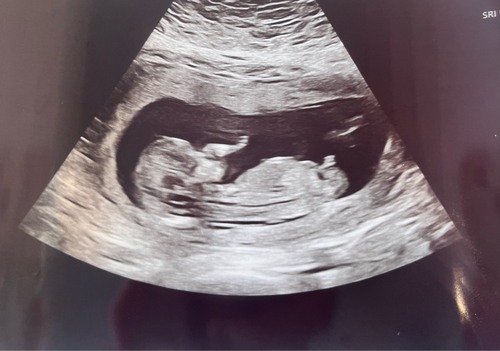

🩷💙🤷🏻‍♀️?

En deze!

Boy